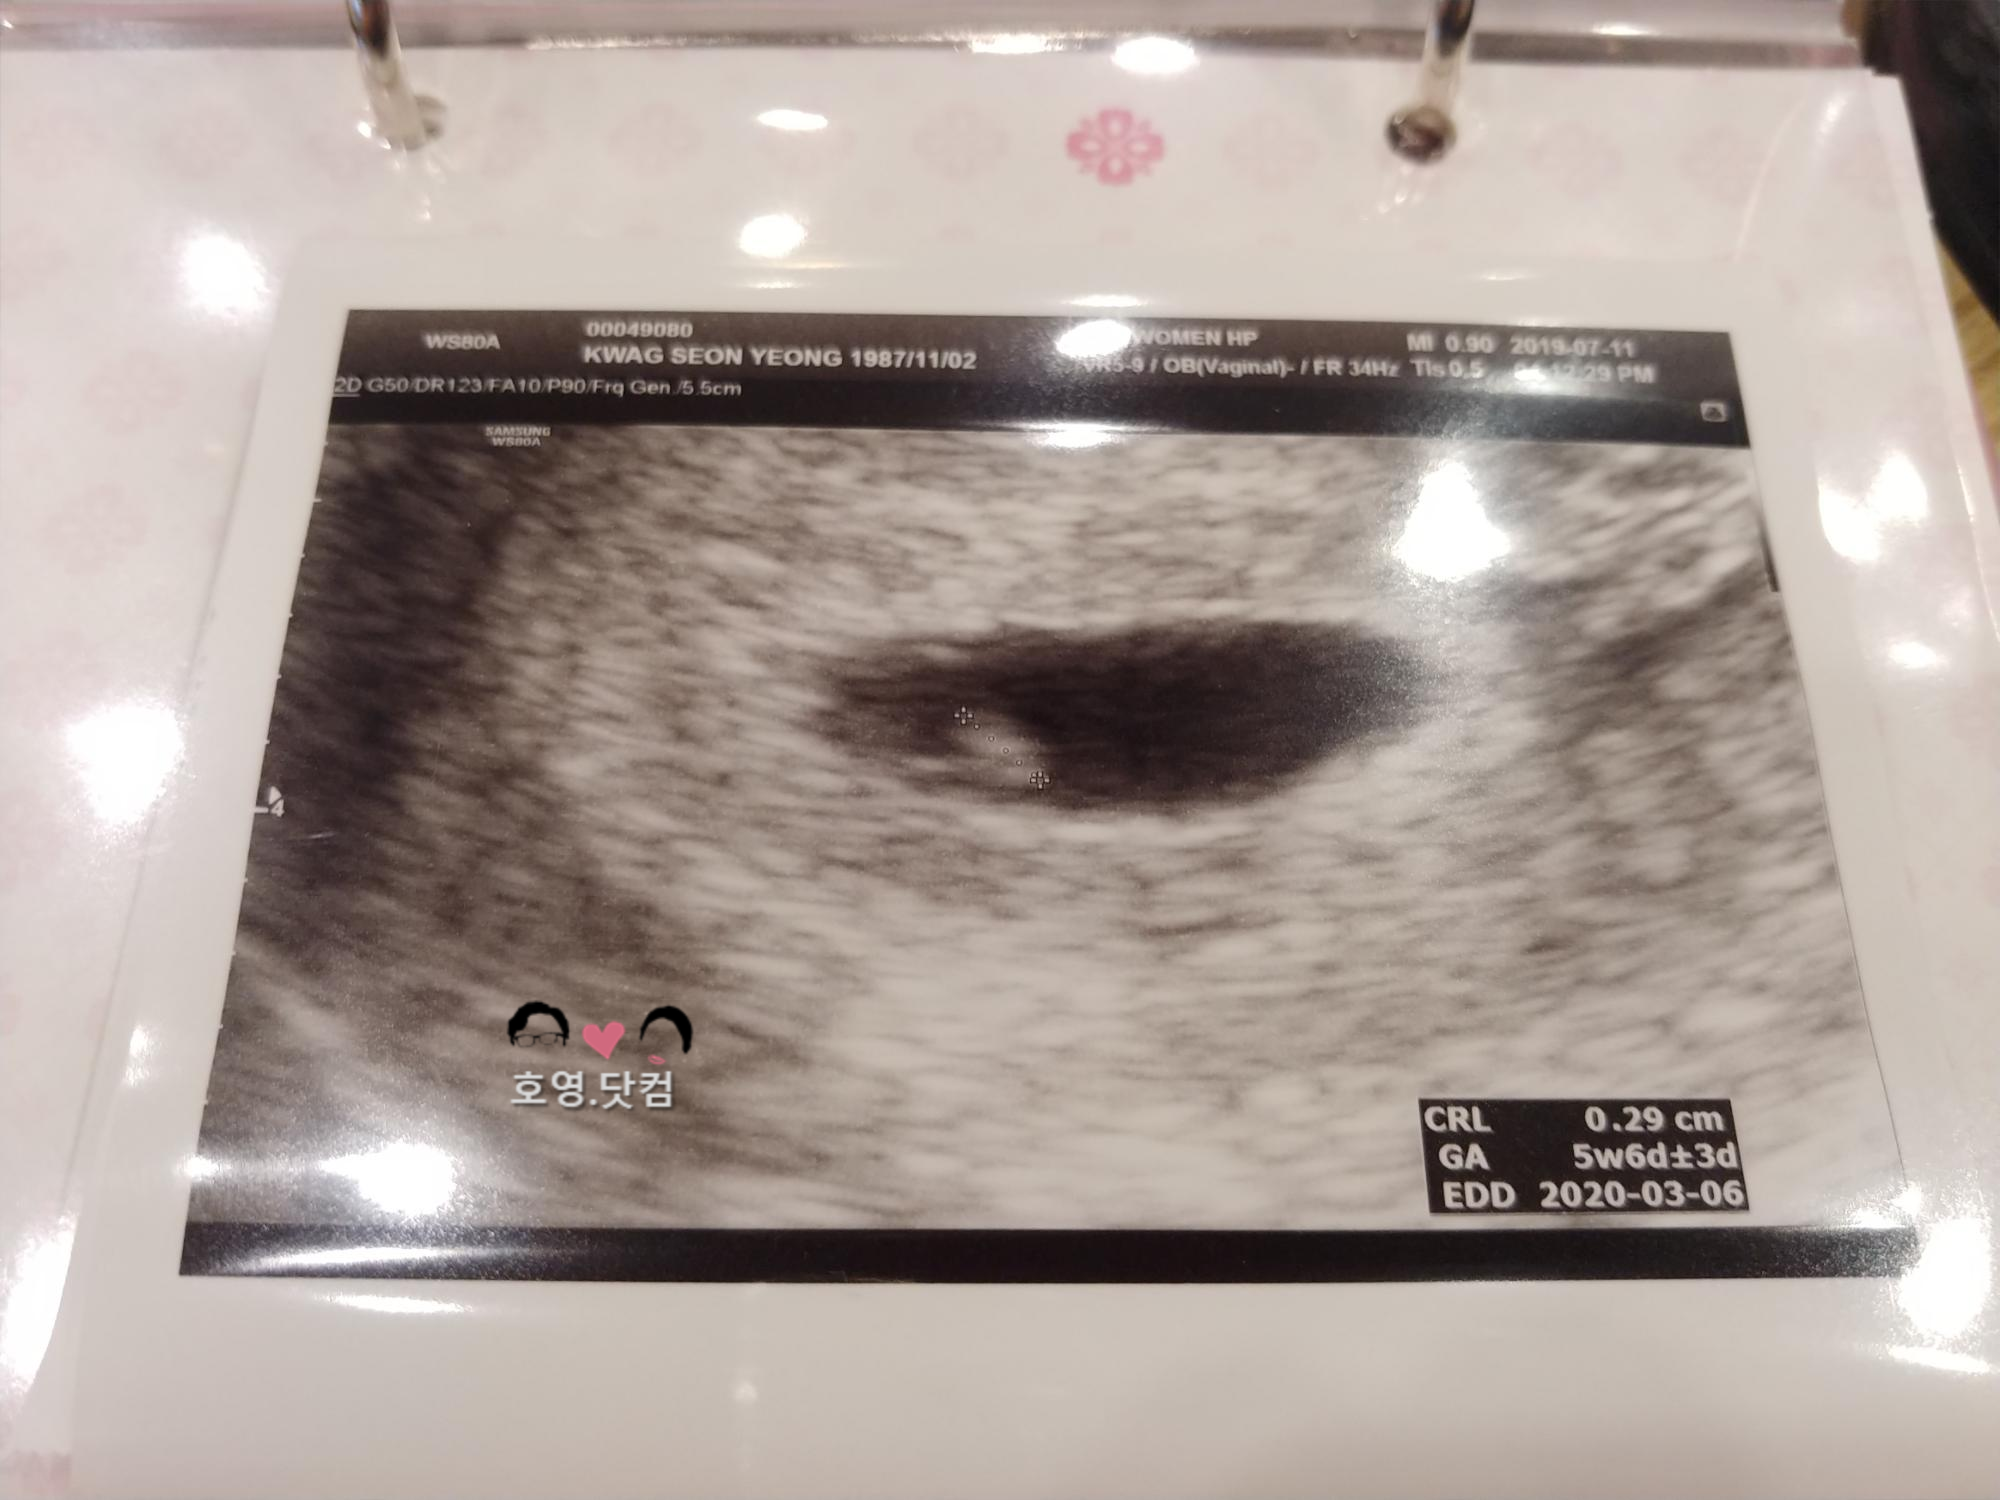

유부유부 이야기/씩씩이:) 19.07.11 몰래 온 손님(?) IamMH 2019. 7. 30. 21:51 19. 07. 11또뇽에게 뜻하지 않게 놀러 온 손님걱정, 놀람, 행복, 눈물복잡 미묘한 감정이 한 순간에 밀려왔다.태명은 씩씩이다. 씩씩하고 건강하게 내년 봄에 만나자. 공유하기 게시글 관리 호♥️영이의 행복한 하루 ;-)